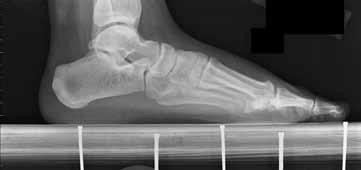

Question 9

A 72-year-old female with cuff tear arthropathy undergoes a reverse total shoulder arthroplasty (rTSA) using a Grammont-style prosthesis.

How does this classic implant design primarily alter the biomechanics of the shoulder to improve active elevation?

Explanation

The classic Grammont-style reverse total shoulder arthroplasty (rTSA) alters shoulder biomechanics by medializing and distalizing the center of rotation. This effectively lengthens the deltoid muscle (increasing its tension) and significantly increases its moment arm, allowing the deltoid to effectively elevate the arm in the absence of a functional rotator cuff.